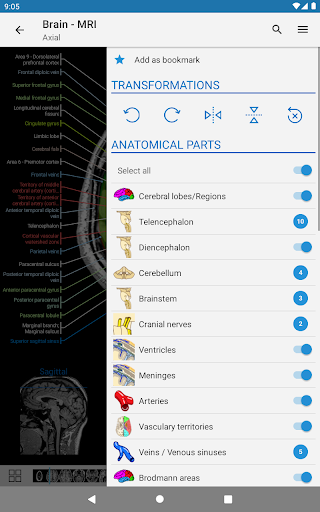

- Seleccione las etiquetas anatómicas por categoría

- Ahora puede ocultar las estructuras una por una (nuevo botón dentro de la ventana emergente de descripción) y visualizarlas nuevamente en el menú derecho